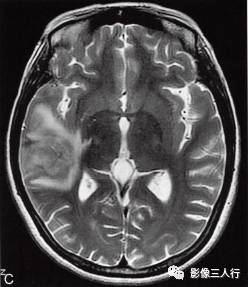

图1右颞叶横纹肌样脑膜瘤

A.T1WI横断面;B、C.T2WI横断面;D、E、F、G.增强横断面、矢状面、冠状面;H.HE×100

图1A:MRI T1WI示,右侧颞叶不规则形肿块,信号欠均匀,为稍低信号与小斑片状稍高信号混杂。其累及颞叶灰白质,界限欠清、边缘不整,大小约4.1cm×4.3cm×5.1cm。邻近脑沟脑裂变浅变平,周边脑实质受压。图1B、C:T2WI示,右颞不规则形肿块,信号欠均匀,为稍高信号与小斑片状略低信号混杂。灶周见带状高信号脑水肿。图1D~G:T1WI C示,右侧颞叶肿块呈不均匀的多个结节块状明显强化,邻近脑膜为线条状强化、增厚。